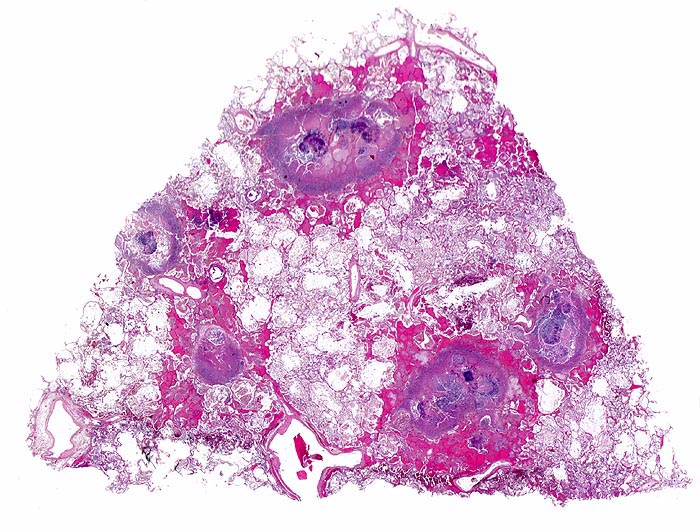

Aspergilluspneumonie

Lunge

Multiple Herde mit zentraler Nekrose und hämorrhagischem Randsaum mit Fibrinexsudaten. Im Zentrum der Herde sind Pilzmyzelien nachweisbar.

Seit 14 Monaten bekannte chronische lymphatische Leukämie behandelt mit Chemotherapie. Der Patient entwickelt unter Therapie eine Pneumonie und verstirbt an einer Pilzsepsis.

Histologie

Scan